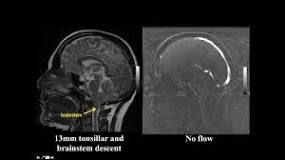

- Chiari malformation: To assess CSF dynamics in the subarachnoid space, which can be abnormal in these cases.

CINE MRI STUDY

What does a cine MRI show?